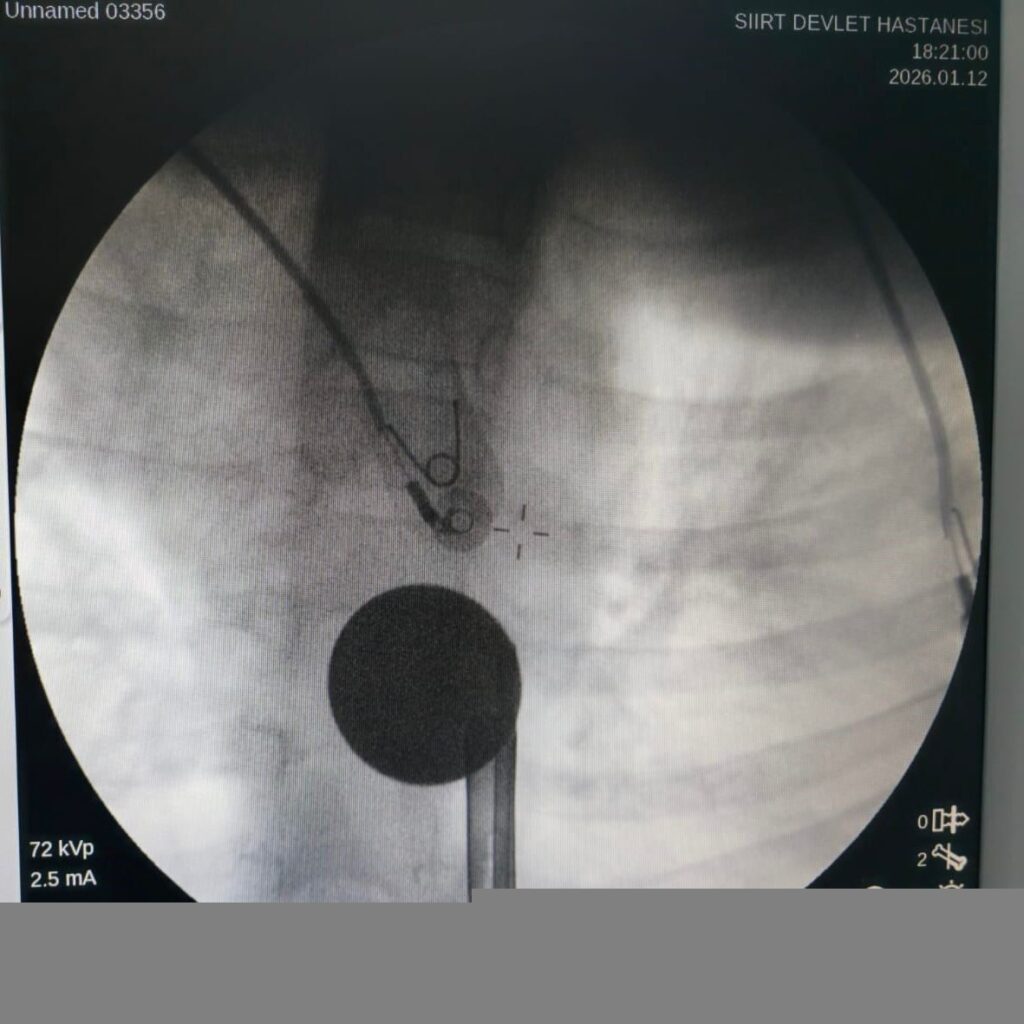

Siirt’te 8 yaşındaki çocuk, boğazına kaçan madeni para sayesinde hastanede kurtarıldı.

Siirt'te 8 yaşındaki Y.K., boğazına madeni 5 lira kaçması sonucu hastaneye kaldırıldı.…